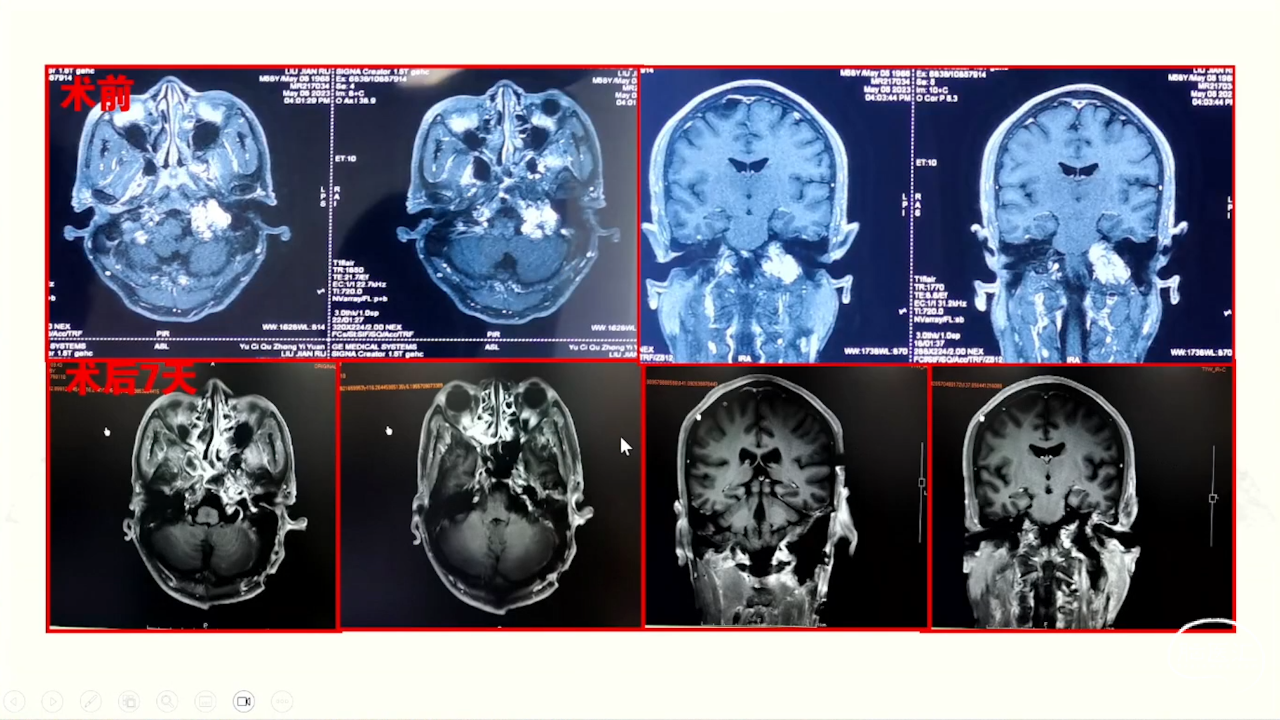

卜博教授:颈静脉孔区肿瘤:解剖及156例经验

颈静脉孔区肿瘤充分显露是硬道理。肿瘤越大,工作通道越宽。颈静脉孔扩大越明显,开放颈静脉孔越容易。